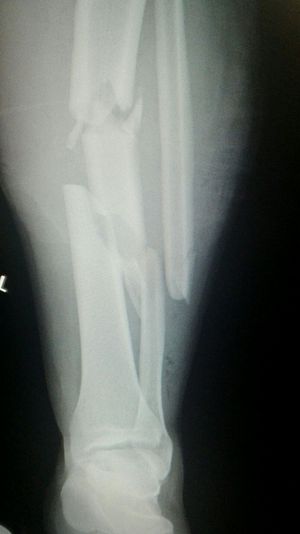

Accident

Leg

Fractures

Motorbike

220kmh